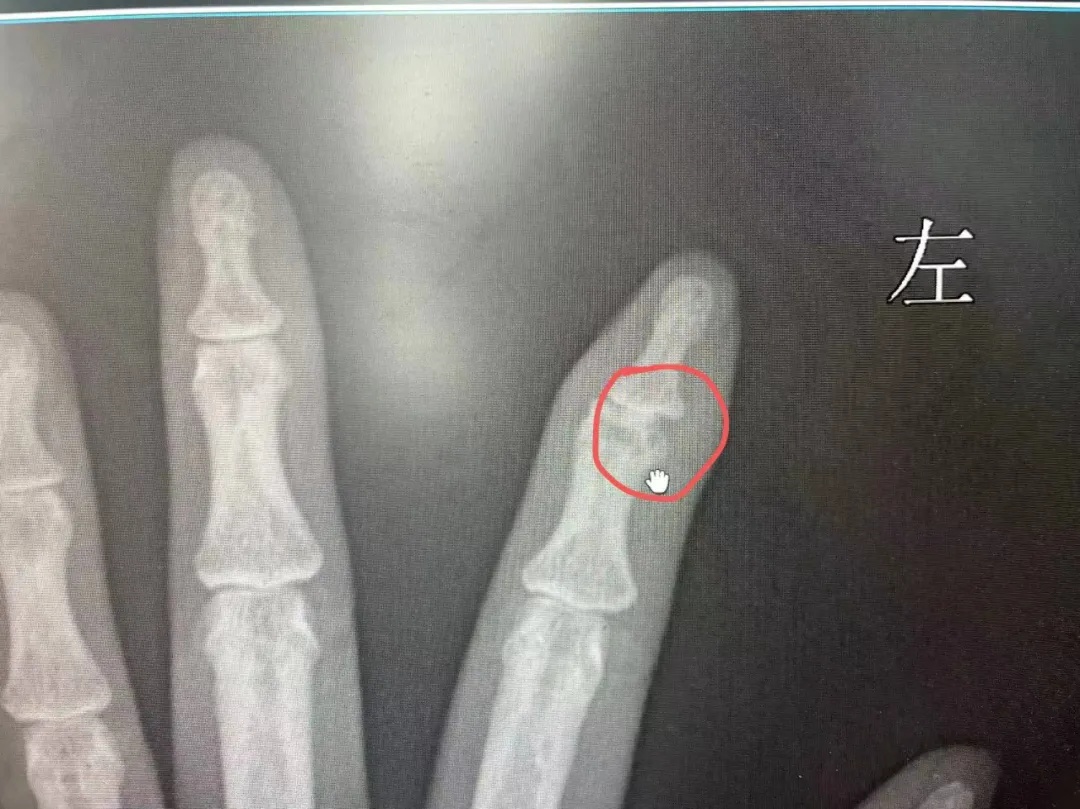

在长沙市第三医院就诊检查后,谢先生被诊断为左中指感染,并已出现皮肤软组织坏死,如不及时治疗,还可能引发其他并发症,如败血症、骨髓炎等,甚至可导致截指。谢先生不得不住院接受进一步治疗。

据接诊的武汉市第四医院古田院区手外科医生陈海仁介绍,这名患者指骨远节有近1厘米长的细菌侵蚀导致的骨质破坏,若继续感染,骨髓炎越来越严重,有可能手指不保。